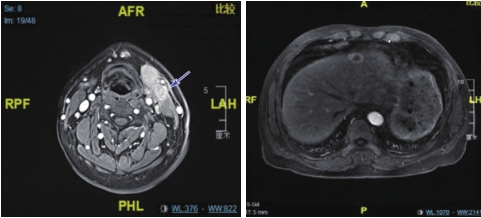

腹部MRI(2020-04-08):肝左叶结节,符合转移瘤MRI表现(图1)。

图1 喉MRI、腹部MRI(治疗前)

提示梨状窝占位、左颌下淋巴结肿大、左上颈淋巴结肿大、肝左叶转移病灶